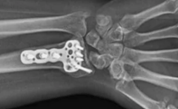

The surgeon who operated on my wrist commented that I was in good health for someone who hadn’t needed a doctor for so many years. Then he positioned a titanium plate and nine screws in my broken wrist bone to join fractures and to support it. Even today I must be careful not to knock it against something. But once again I knew that my Lord cares for me in troubled times and answers prayer!